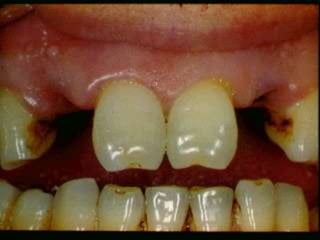

Acute ulcerative	SyphilisCongenital syphilisHutchinson’s incisors, “moon’s molars”	Primary		painless, indurated, ulcerated, usually involving the lips, tongue	Secondary- mucous patches, split papules	Tertiary- Gummas, can involve palate, tongue